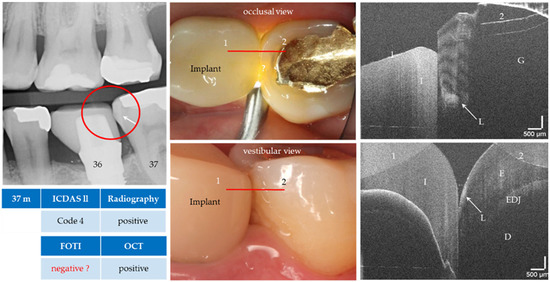

Figure 13.

Tooth 37 (m). Apart from the FOTI, the enamel lesion (L, arrows) next to a gold inlay (G) was detected visually, radiographically and by OCT from both the occlusal and vestibular position. The proband was also able to confirm that a non-cavitated lesion had been detected before insertion of the implant crown (I, e.max CAD). The red lines mark the OCT cross-sectional planes. As a result of focusing on deeper structures, the tooth surface has flipped in the OCT images. Enamel (E), dentin (D), enamel-dentin junction (EDJ). The vertical scales are related to the refractive index n = 1.0 (see remark in Figure 4).